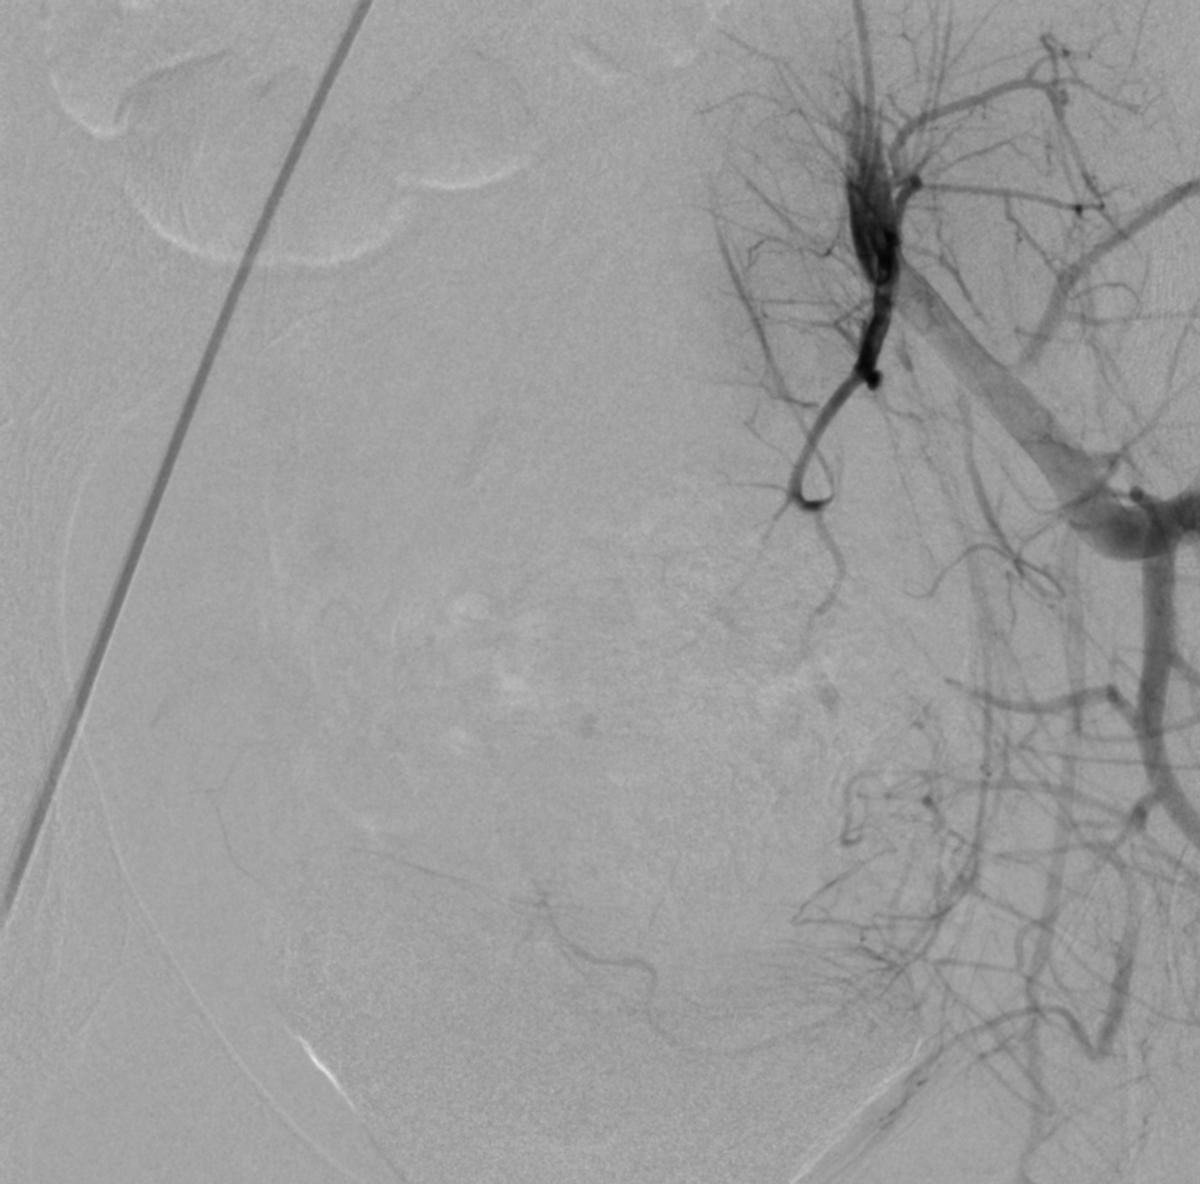

患儿完成入院前术前检查,并进行了全科的术前讨论。结合患儿体征及相关的术前检查,目*考前**虑PROS综合症。目前主要解决的是月经出血的问题,可以通过栓塞双侧子宫动脉来进行治疗。患儿全麻后,使用5F穿刺针行右股动脉穿刺,成功后置入5F血管鞘,导丝引导下置入5F Headhunter Angiopointer造影导管,在导丝引导下选入髂内动脉,进入子宫动脉,造影见左侧子宫动脉远端纤细,右侧子宫动脉螺旋增粗,微导丝引入微导管进入子宫动脉,使用聚乙烯醇颗粒栓塞剂350um-560um,栓塞微粒球(300-500um)分别行双侧子宫动脉栓塞,栓塞后造影未见子宫动脉远端分支显影。

栓塞术后造影